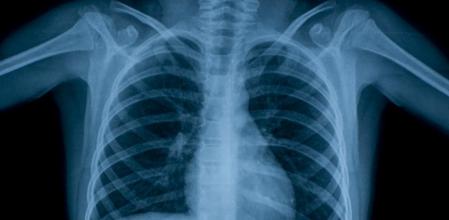

Cada 60 segundos, 20 personas desarrollan en todo el mundo la enfermedad y tres mueren por su culpa. Su causa es la tuberculosis. En España nos retrotrae a la posguerra, a un problema de la época de nuestros padres o abuelos. Una noticia vieja o un documental histórico. En realidad, la tuberculosis está muy viva y sigue matando. Lejos de estar a punto de erradicarla, probablemente nos encontramos en uno de los momentos de la historia con más casos de la enfermedad en el mundo.

Por ese motivo, este viernes no conmemoramos una efeméride más. Hace 135 años que se descubrió el bacilo que causa la tuberculosis, la enfermedad infecciosa más letal, y cada año sigue habiendo millones de casos, miles en España. La lucha sigue y no podemos bajar la guardia. Necesitamos seguir invirtiendo en investigación para encontrar nuevas herramientas que nos ayuden a combatirla.